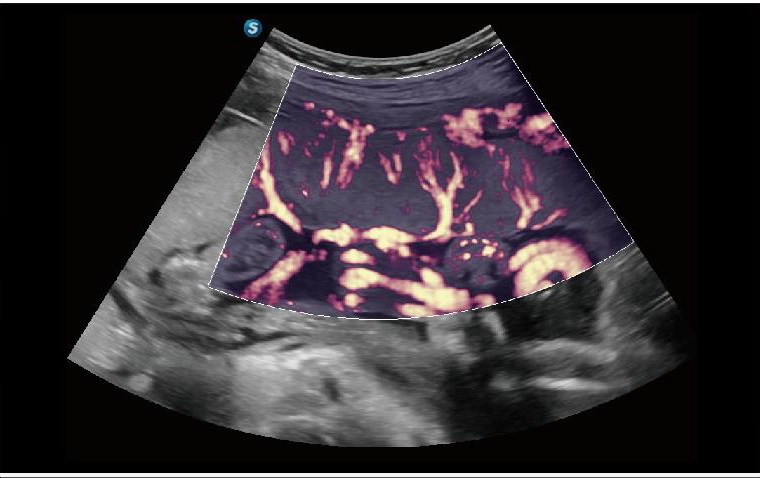

FHR

FHR, organlardaki mikrovasküler yapının gözlemlenmesini artırılmış hassasiyet ve geliştirilmiş çözünürlükle mümkün kılarak, kan dolaşımının gerçek durumunun doğru şekilde temsil edilmesini sağlar.